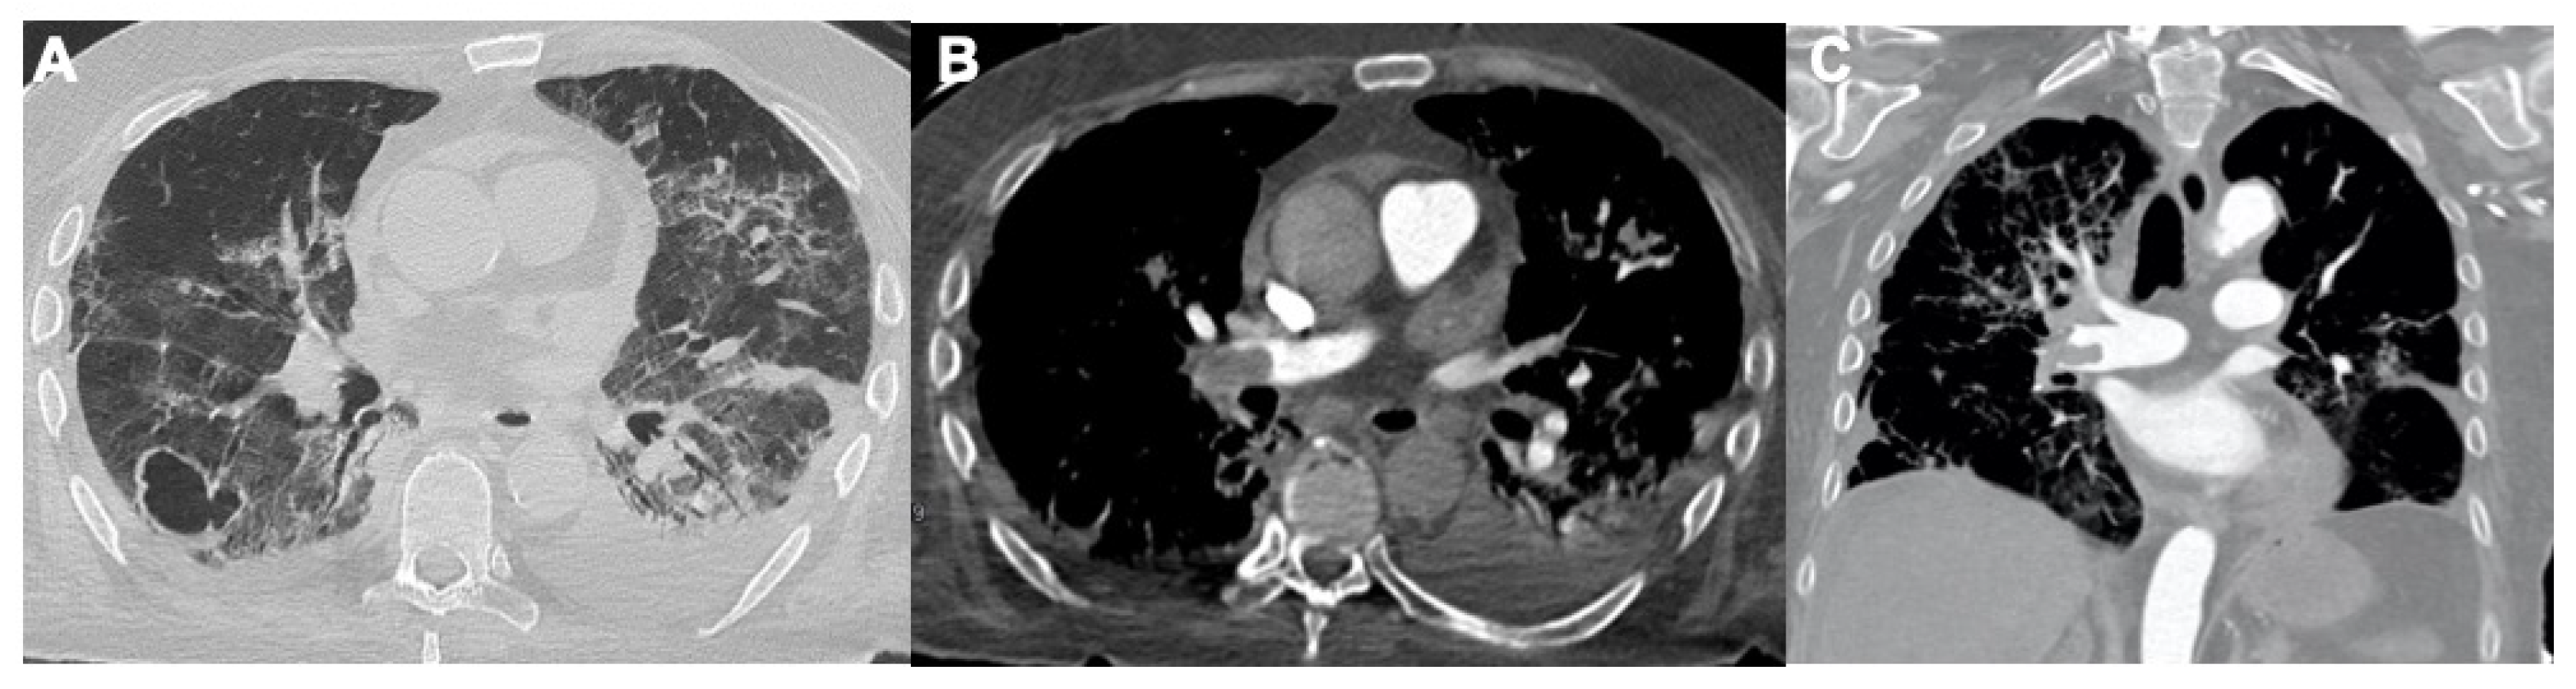

2.2. Acute Respiratory Disease Syndrome

2.3. Pulmonary Embolism